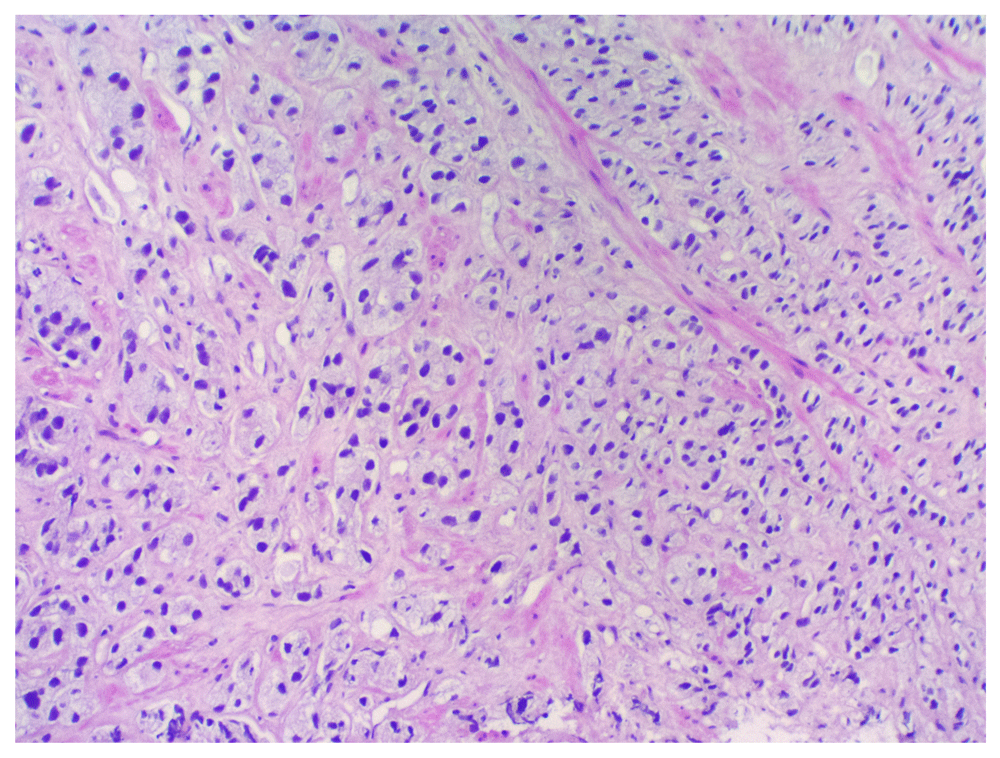

The right breast histopathological assessment. Histopathological examination showed an infiltrating duct carcinoma (Figure 3), with a Nottingham combined histopathological grade of 1/3 (tubules 1, pleomorphism 2 and mitoses 1). Estrogen and progesterone receptors were expressed diffusely within the tumour cells (Figure 4). Foci of low-grade cribriform ductal carcinoma in situ were also evident (Figure 5). The PSA immunochemistry staining was negative confirming primary breast carcinoma.